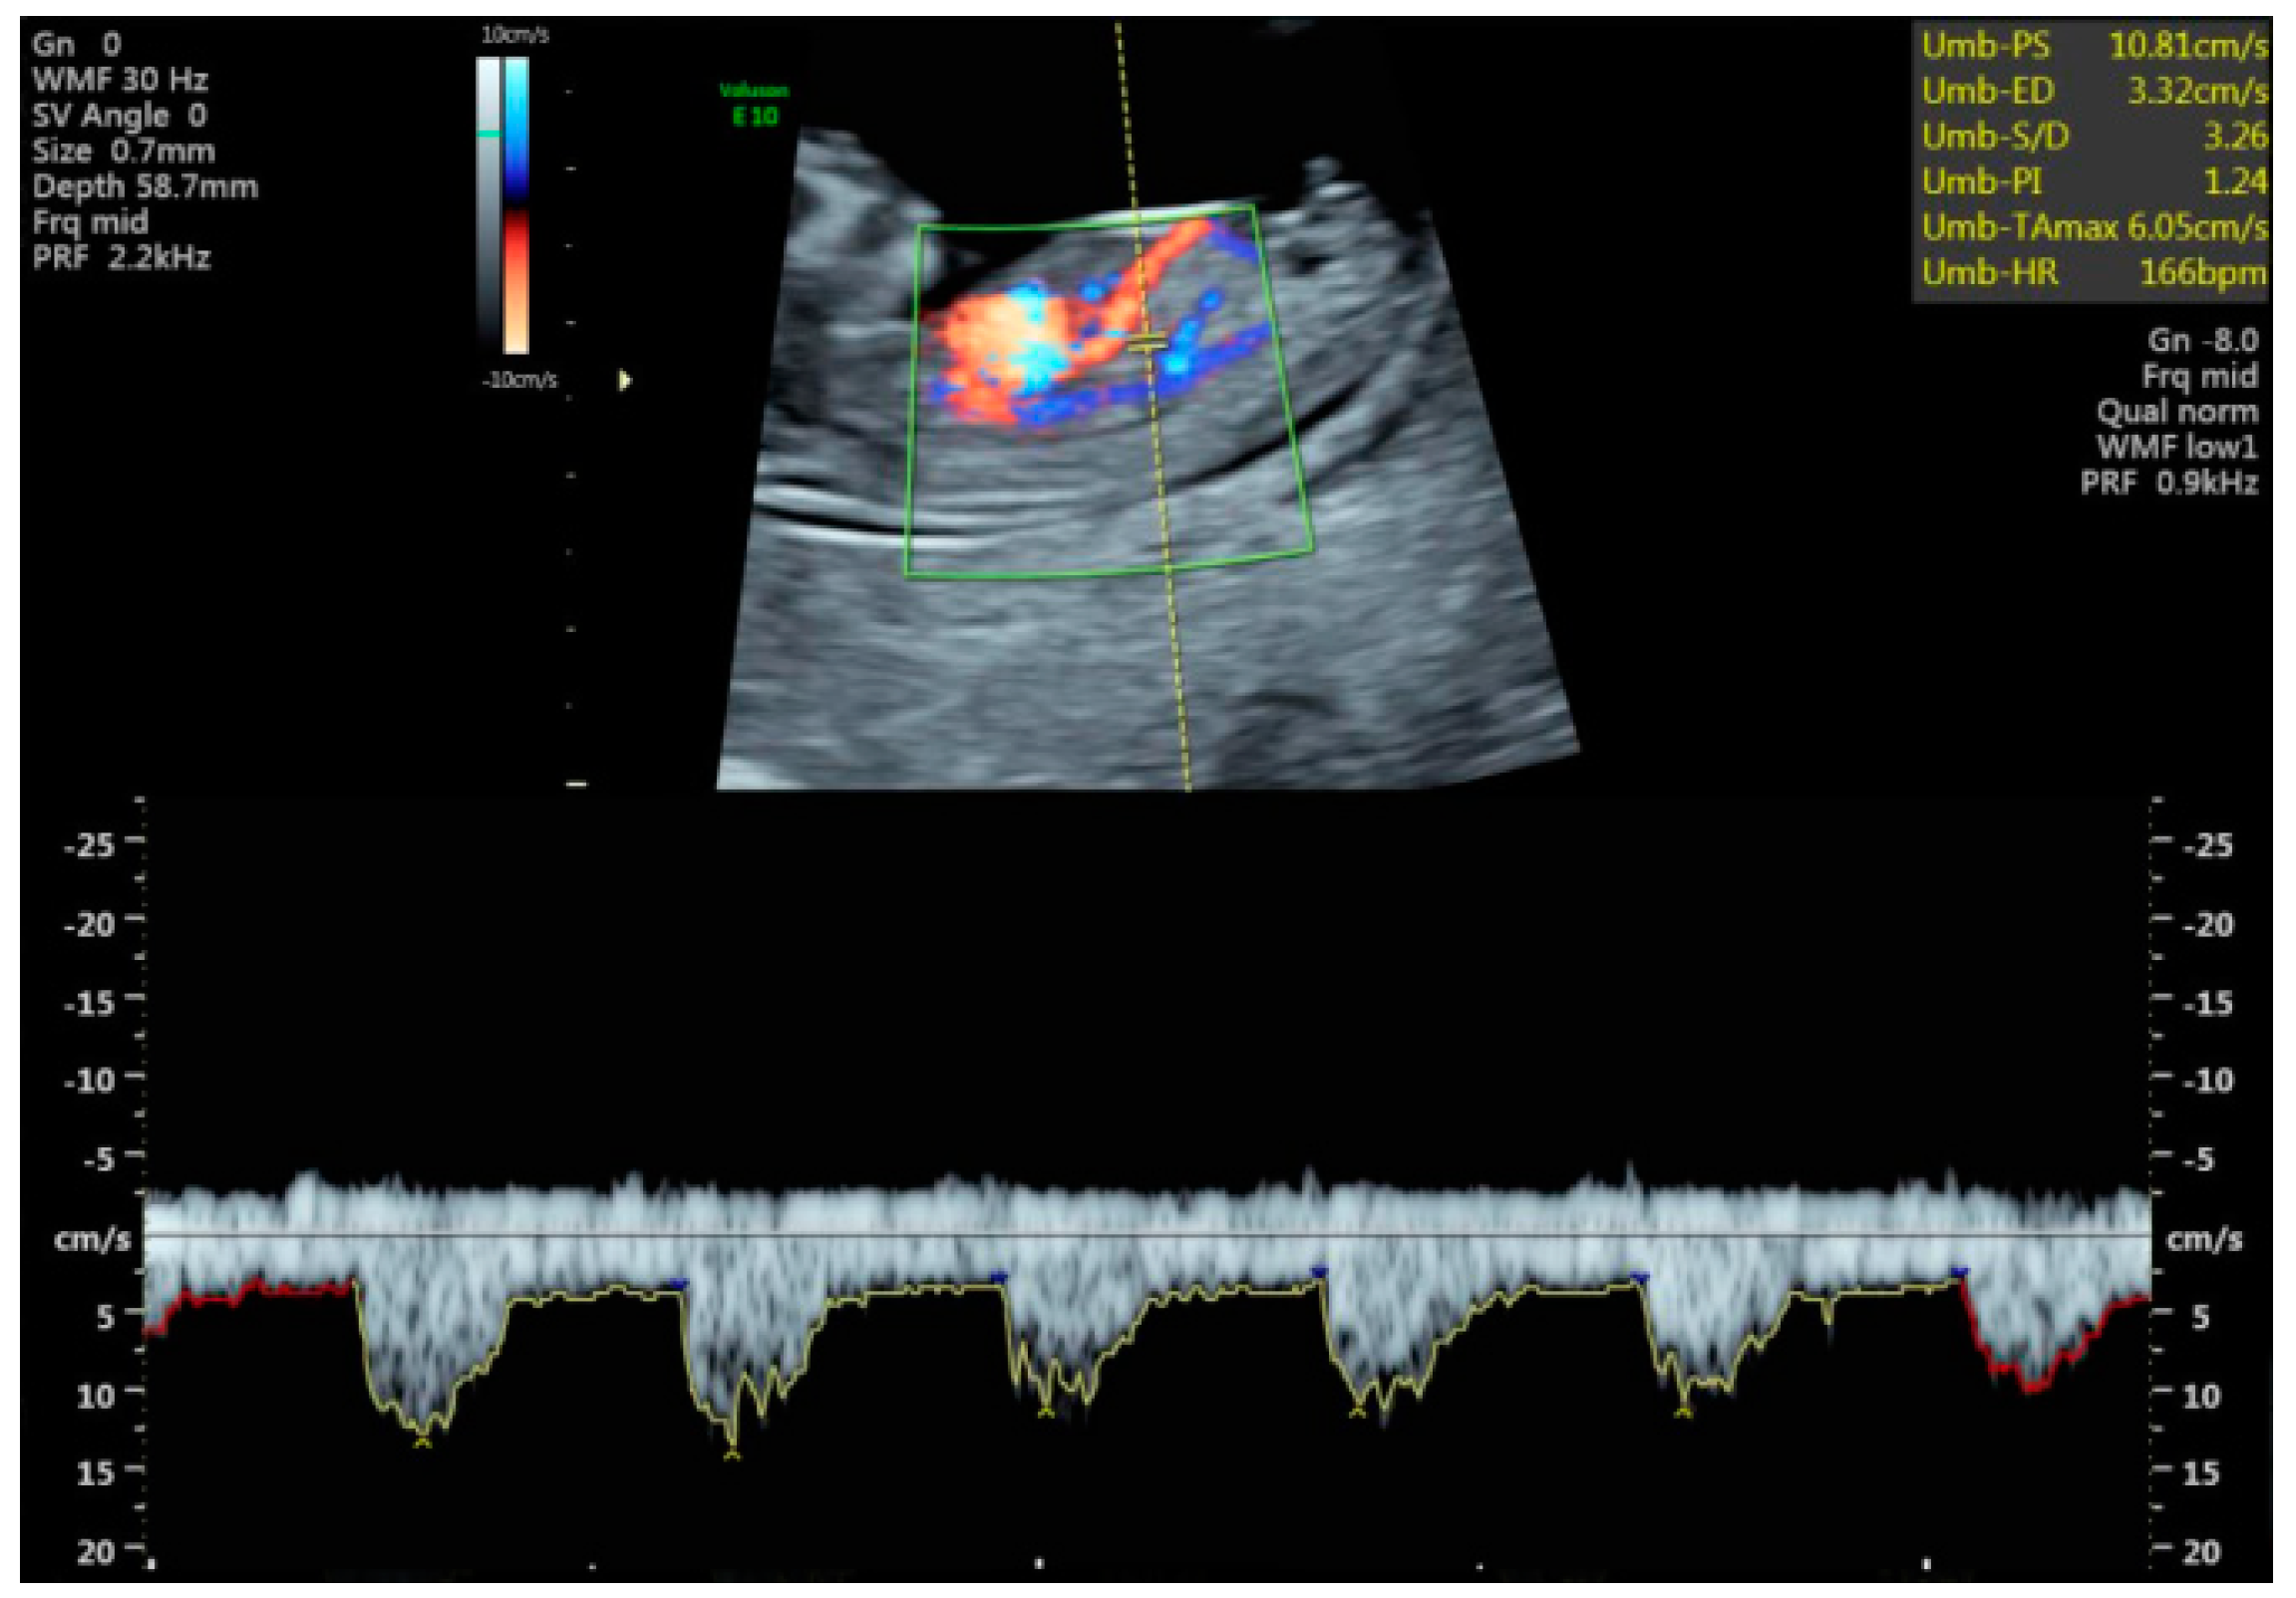

Figure 1 shows an image of a normal hepatic artery flow.

Figure 1.

Longitudinal plane view of 12-week fetus showing the umbilical vein, the ductus venosus and the descending thoracic aorta on color flow. The hepatic artery is the vessel coming into close contact with the ductus venosus.